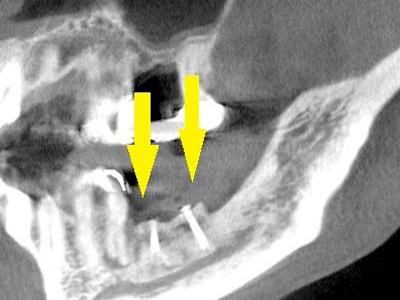

患者様は50代男性。インプラント治療前のレントゲン写真です。

右下顎大臼歯2本の抜歯後のレントゲン写真で、写真の黄色矢印は、歯の周囲の歯槽骨が大きく吸収されてしまっていました(黄色矢印)。 -

CTで見ると、骨吸収の様子が良く分かり、下顎骨の中を通る神経近くまで骨がありませんでした(黄色矢印)。